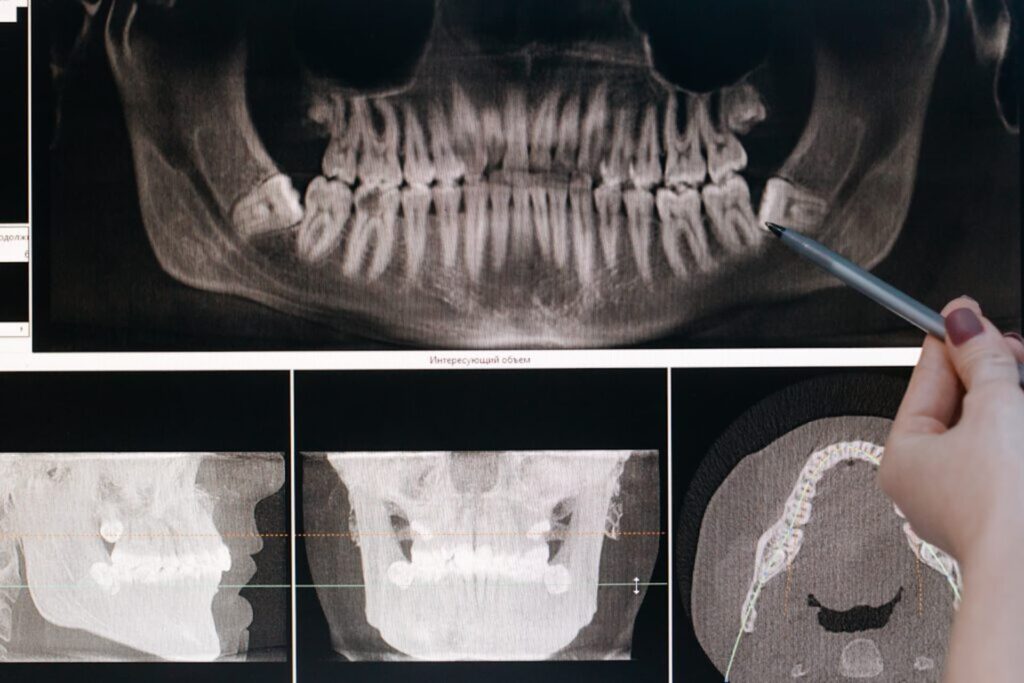

Das Kiefergelenk / CMD

In den letzten Jahren hat das Kiefergelenk viel Aufmerksamkeit erfahren. Zahnärzte, Orthopäden und Kieferchirurgen haben sich förmlich darauf gestützt. Als Manualtherapeutin habe ich schon vor Jahren in meinen Fortbildungen gelernt, dass das Kiefergelenk einen enormen Einfluss auf unsere Statik hat. Leider auch am eigenen Leib. Daher erzähle ich euch mal in diesem Blog meine Geschichte. […]